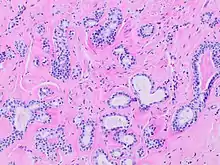

Human submandibular gland. At the right is a group of mucous acini, at the left a group of serous acini.

Histopathology of sclerosing adenosis of the breast.